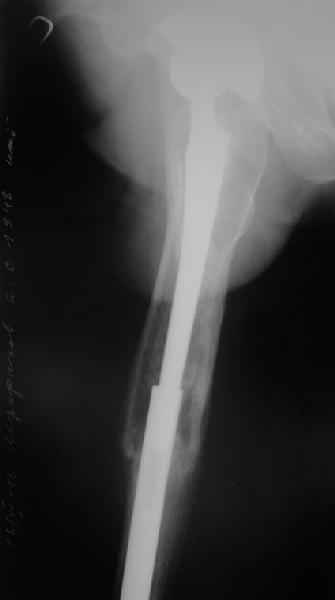

Произведено закрытое удлинение ножки эндопротеза с помощью ретроградного интрамедуллярного стержня. Продолжительность операции 3 часа. Два из них закрытое восстановление длины бедра диистрактором

таз-бедро.

А нельзя ли увидеть и профиль бедра на всем протяжении, т.е. и весь протез, и весь стержень? И фас бы с коленом.

Спасибо!

новые снимки

|